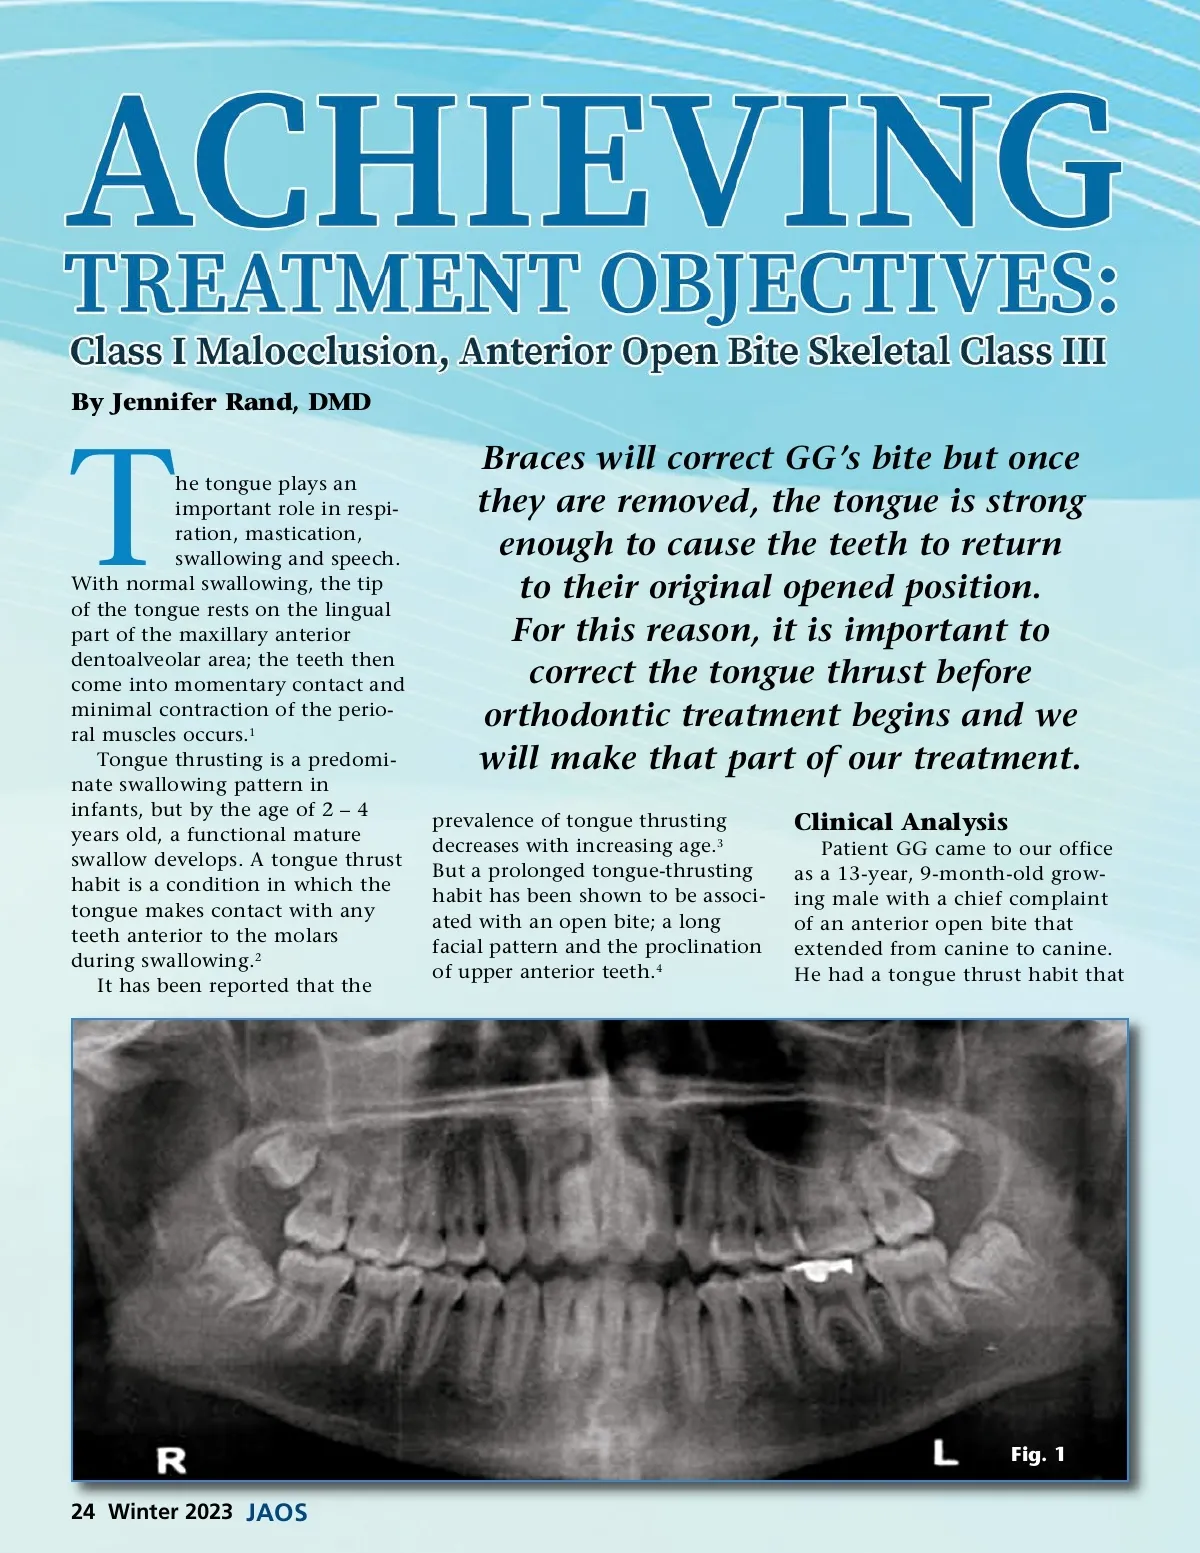

By Jennifer Rand, DMD T he tongue plays an important role in respi-ration, mastication, swallowing and speech. With normal swallowing, the tip of the tongue rests on the lingual part of the maxillary anterior dentoalveolar area; the teeth then come into momentary contact and minimal contraction of the perio-ral muscles occurs. 1 Tongue thrusting is a predomi-nate swallowing pattern in infants, but by the age of 2 – 4 years old, a functional mature swallow develops. A tongue thrust habit is a condition in which the tongue makes contact with any teeth anterior to the molars during swallowing. 2 It has been reported that the Braces will correct GG’s bite but once they are removed, the tongue is strong enough to cause the teeth to return to their original opened position. For this reason, it is important to correct the tongue thrust before orthodontic treatment begins and we will make that part of our treatment. prevalence of tongue thrusting decreases with increasing age. 3 But a prolonged tongue-thrusting habit has been shown to be associ-ated with an open bite; a long facial pattern and the proclination of upper anterior teeth. 4 Clinical Analysis Patient GG came to our office as a 13-year, 9-month-old grow-ing male with a chief complaint of an anterior open bite that extended from canine to canine. He had a tongue thrust habit that Fig. 1 24 Winter 2023 JAOS